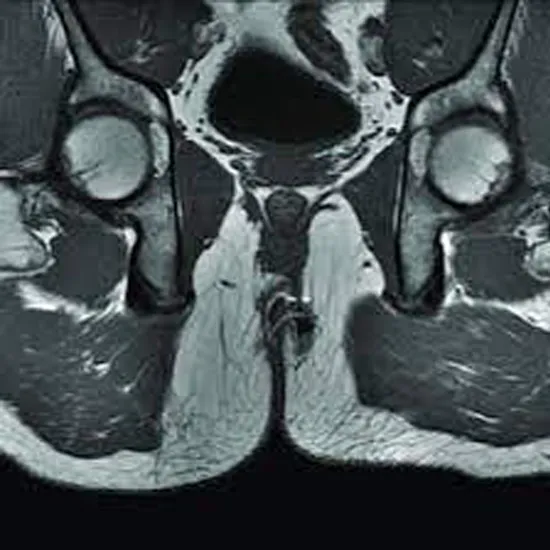

MRI (Magnetic Resonance Imaging) Screen Fistulography is a non-invasive diagnostic procedure to check fistula for abnormal passages between the body parts that drain out of your skin.

MRI fistulography has been a valuable and suggested screening tool in pathology due to its efficacy in assessing perianal fistulous tracts in soft tissues.

The doctor uses a tiny catheter in your fistula graft then contrast is injected into the tube to get detailed images.  MRI for Fistulogram is an imaging system used to develop a view of the sphincter muscles, the anal canal, and the soft tissues around it.